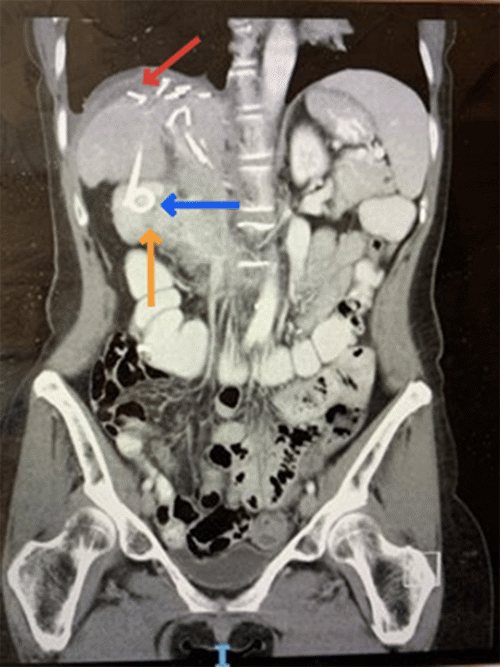

She was discharged to the ward on day 2. On day 3, the surgeon on the morning ward round noted 490 ml of intermittent bilious output from her drain as her synthetic liver function deteriorated. Endoscopic retrograde cholangiopancreatography was considered, and an expectant approach was adopted as the bile leak did not persist. Her liver function improved to baseline during her admission, but on day 12, in the setting of increasing fever and inflammatory markers, a CT of the abdomen and pelvis was performed (Figure 1). This demonstrated a 7.1 cm subcapsular collection with the drain tip positioned at its inferior aspect. She was placed on intravenous antibiotics and underwent an attempted percutaneous catheter (14 Fr Navarre) drainage of the collection (Figure 2). The procedure was completed successfully under adequate sedation. Unfortunately, however, the patient experienced severe pain refractory to analgesia during recovery.

Figure 1. Coronal View CT Abdomen and Pelvis Demonstrating Right Subphrenic Collection. Published with Permission